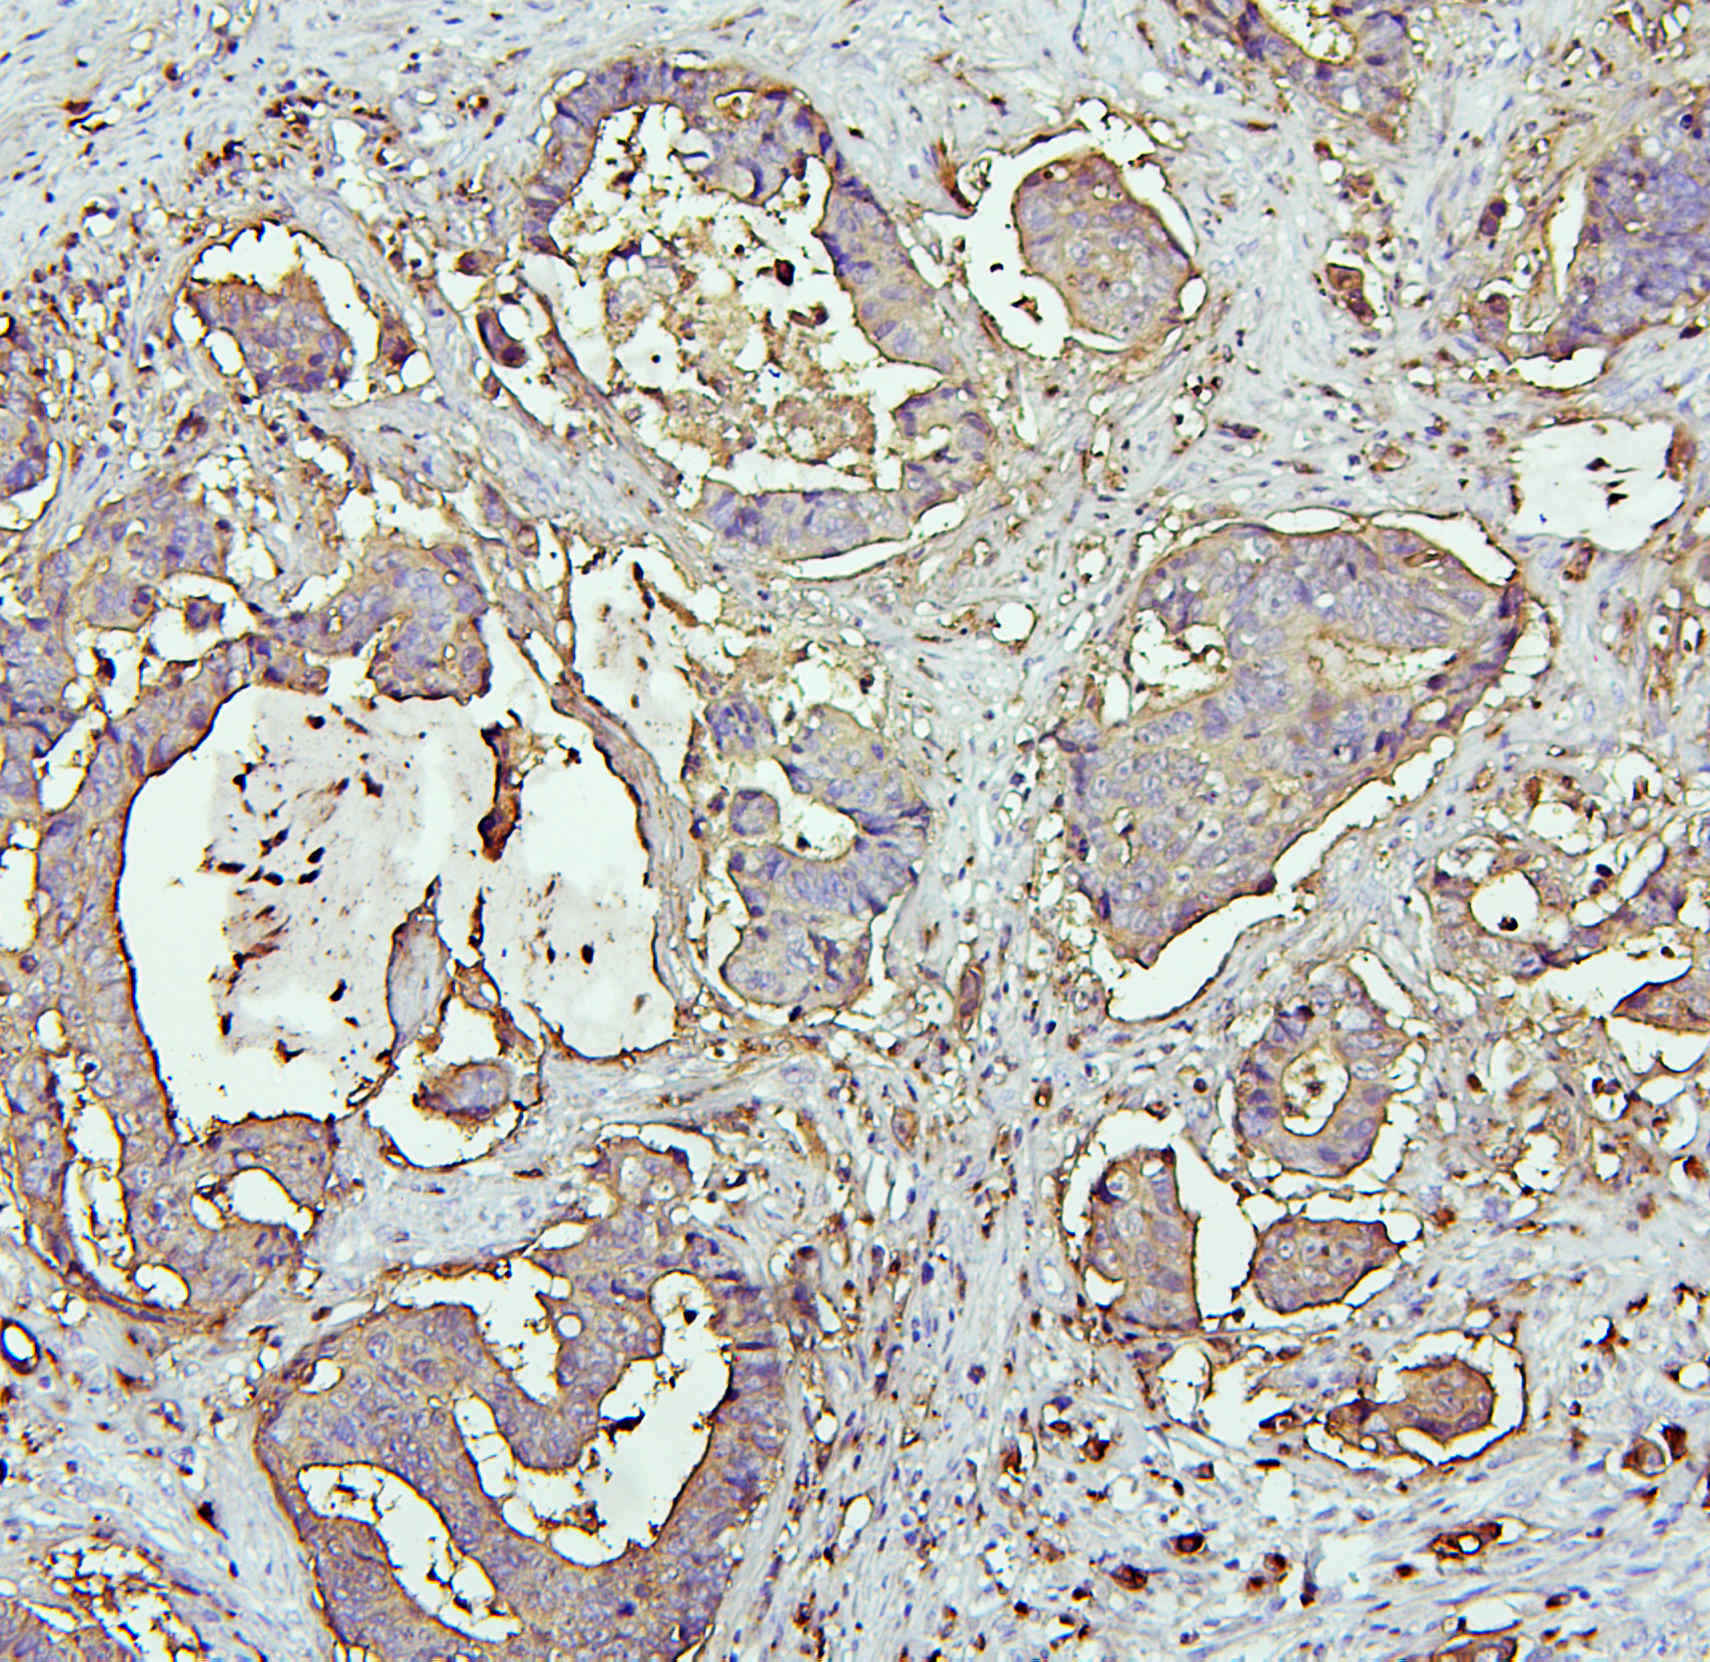

IHC analysis of CEA/CEACAM5 using anti-CEA/CEACAM5 antibody (A00356).

CEA/CEACAM5 was detected in a paraffin-embedded section of human colon cancer tissue. Biotinylated goat anti-rabbit IgG was used as secondary antibody. The tissue section was incubated with rabbit anti-CEA/CEACAM5 Antibody (A00356) at a dilution of 1:200 and developed using Strepavidin-Biotin-Complex (SABC) (Catalog # SA1022) with DAB (Catalog # AR1027) as the chromogen.